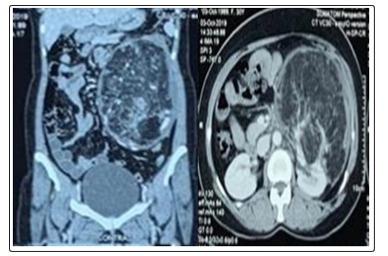

This patient, 28-year-old homemaker, who experienced left flank pain of 3 months duration, and underwent evaluation in her hometown. Ultrasonography (USG) and Contrast Computed Tomography Scan - Kidney Ureter Bladder (CT-KUB) was advised, which showed a left renal giant AML, and patient was referred to our centre for further management. After taking complete history, detailed clinical examination was performed; a palpable lump was noted in the left upper quadrant of the abdomen. There were no stigmata of Tuberous Sclerosis. We discussed with the patient, and her husband about the diagnosis, the available options for the management of this giant AML, and the possibility of need for Nephrectomy. Finally, due to their limited financial backup we took collective decision to go ahead with Left Partial/Simple Nephrectomy and excision of the mass. It was a challenge to plan the approach in this case with no advantage of pre-operative selective angioembolization to minimize the chances of intra-operative bleeding. Subsequently, after examining the available imaging studies, we planned it as a Nephron Sparing Surgery (NSS).

Figure 1: CT-Scan images showing left renal giant AML in coronal view (a) & axial view (b).